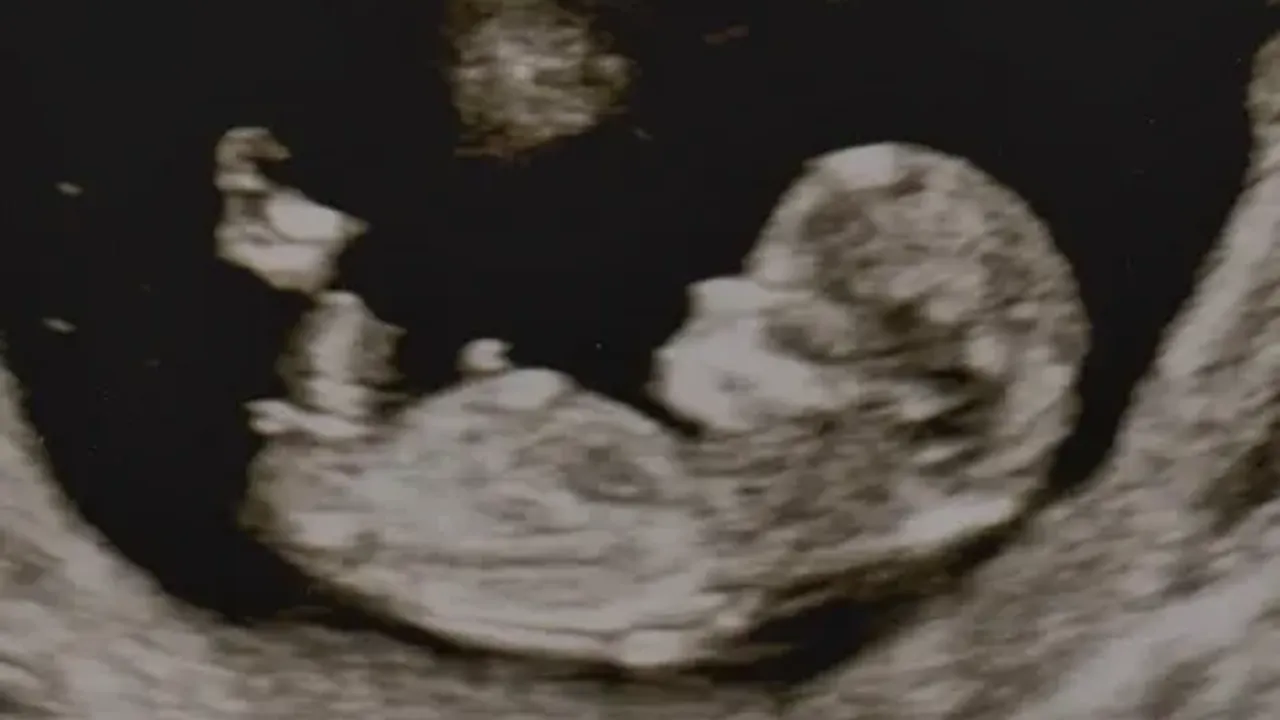

Cinsiyetin Görselleşmesi İçin Neden Daha Fazla Zaman Gerekir?

Bebeğin cinsel organları, gebeliğin 7. haftasından itibaren oluşmaya başlar. Ancak bu erken dönemde hem erkek hem de kız bebeklerin cinsel organları "genital tüberkül" adı verilen küçük bir çıkıntı şeklinde görünür. Bu çıkıntının açısı ve yapısı zamanla farklılaşır:

Bu ayrımın ultrasonla net bir şekilde görülebilmesi için genellikle 16. hafta ve sonrası beklenir. Çoğu doktor, cinsiyet tahmini için en doğru zamanın 18 ile 22. haftalar arasındaki detaylı ultrason muayenesi olduğunu belirtir. Bu dönemde bebeğin pozisyonu uygunsa, dış cinsel organlar daha belirgin hale gelir ve cinsiyet tespiti çok daha kolay ve güvenilir olur.